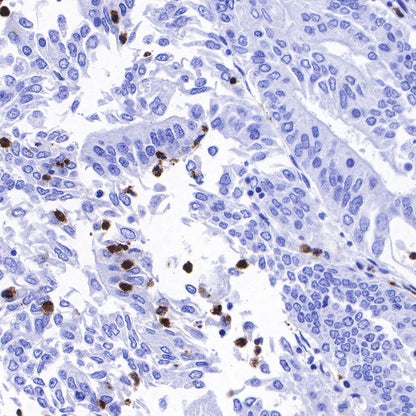

IHC shows positive staining in paraffin-embedded human liver. Anti-Lysozyme antibody was used at 1/100 dilution, followed by a HRP Polymer for Mouse & Rabbit IgG (ready to use). Counterstained with hematoxylin. Heat mediated antigen retrieval with Tris/EDTA buffer pH9.0 was performed before commencing with IHC staining protocol.

IHC shows positive staining in paraffin-embedded human tonsil. Anti-Lysozyme antibody was used at 1/100 dilution, followed by a HRP Polymer for Mouse & Rabbit IgG (ready to use). Counterstained with hematoxylin. Heat mediated antigen retrieval with Tris/EDTA buffer pH9.0 was performed before commencing with IHC staining protocol.

IHC shows positive staining in paraffin-embedded human spleen. Anti-Lysozyme antibody was used at 1/100 dilution, followed by a HRP Polymer for Mouse & Rabbit IgG (ready to use). Counterstained with hematoxylin. Heat mediated antigen retrieval with Tris/EDTA buffer pH9.0 was performed before commencing with IHC staining protocol.

IHC shows positive staining in paraffin-embedded human colon cancer. Anti-Lysozyme antibody was used at 1/100 dilution, followed by a HRP Polymer for Mouse & Rabbit IgG (ready to use). Counterstained with hematoxylin. Heat mediated antigen retrieval with Tris/EDTA buffer pH9.0 was performed before commencing with IHC staining protocol.

IHC shows positive staining in paraffin-embedded human ovarian cancer. Anti-Lysozyme antibody was used at 1/100 dilution, followed by a HRP Polymer for Mouse & Rabbit IgG (ready to use). Counterstained with hematoxylin. Heat mediated antigen retrieval with Tris/EDTA buffer pH9.0 was performed before commencing with IHC staining protocol.

IHC shows positive staining in paraffin-embedded human lung squamous cell carcinoma. Anti-Lysozyme antibody was used at 1/100 dilution, followed by a HRP Polymer for Mouse & Rabbit IgG (ready to use). Counterstained with hematoxylin. Heat mediated antigen retrieval with Tris/EDTA buffer pH9.0 was performed before commencing with IHC staining protocol.

IHC shows positive staining in paraffin-embedded human endometrial carcinoma. Anti-Lysozyme antibody was used at 1/100 dilution, followed by a HRP Polymer for Mouse & Rabbit IgG (ready to use). Counterstained with hematoxylin. Heat mediated antigen retrieval with Tris/EDTA buffer pH9.0 was performed before commencing with IHC staining protocol.